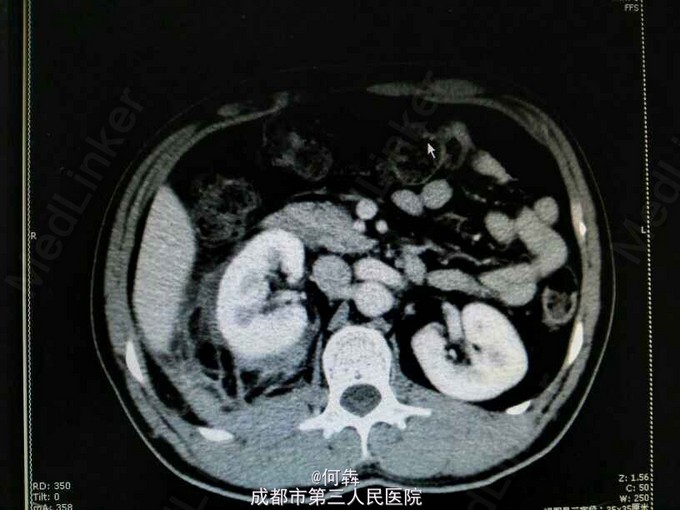

48岁男性,因“突发右腰痛1小时”入院,无血尿、外伤。既往无高血压、糖尿病。

右肾区扣痛阳性,余阴性。

右肾占位伴出血。入院后6天在全麻下行右肾部分切除术。术中冰冻及术后病检见图片